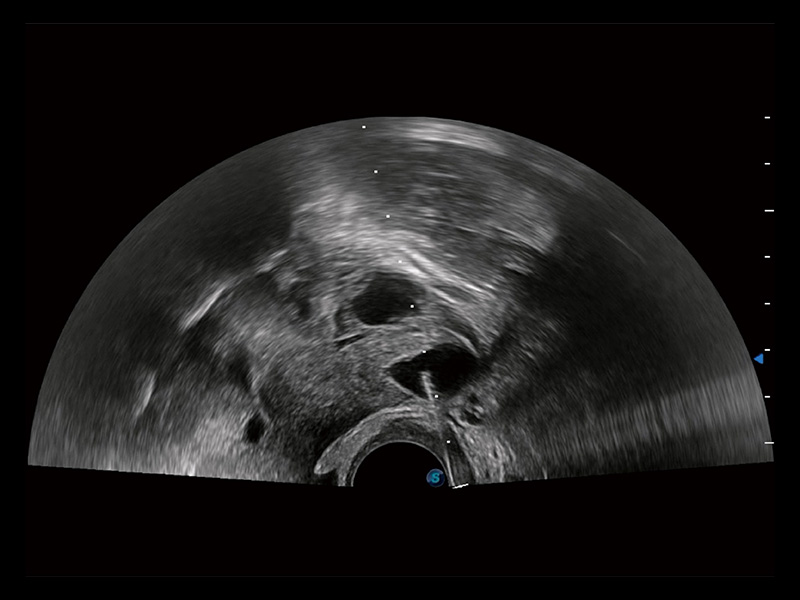

“生育问题”即关系民族复兴,也关系亿万家庭的幸福。随着婚育年龄推迟、社会压力增加等因素,越来越多人群也面临着“生不出、生不好”的问题。辅助生殖作为治疗不孕不育最有效的方法之一,也逐渐成为育儿新希望。而超声检查能为生殖需求人群的初诊评估提供宝贵的信息。 P20 Elite是狗万官方网站匠心打造的一款生殖应用型彩超。她继承狗万官方网站高端极光平台,突破性地将多款新型芯片及硬件模块进行整合,均衡了高端系统性能与小巧灵动机身。P20 Elite卓越的图像质量搭载专科探头,旨在为您提供全面的辅助生殖解决方案。

P20 Elite配备了丰富的生殖探头群和临床应用功能,在卵泡监测、穿刺取卵、胚胎移植、妊娠确认等领域,为生殖需求人群提供了新的临床机会,重新定义高端超声如何应用于生殖健康检查。